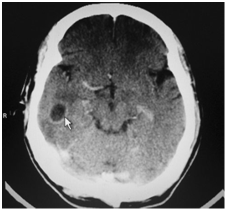

In cases of brain abscesses, although the MRI gives better detail regarding the abscess itself, a CT scan gives valuable information about bony erosion of the mastoid, and can help in determining the cause of the abscess and the most appropriate treatment options (Figure 6–9).

Figure 6 CT scan of brain showing (arrow) hypodense lesion in the right temporal lobe.

Figure 7 CT scan with contrast showing (arrow) ring enhancing lesion in the right temporal lobe.

Figure 8 CT scan with contrast showing ring enhancing lesion in the right temporal lobe.

Figure 9 CT scan showing cerebellar abscess on the right side.